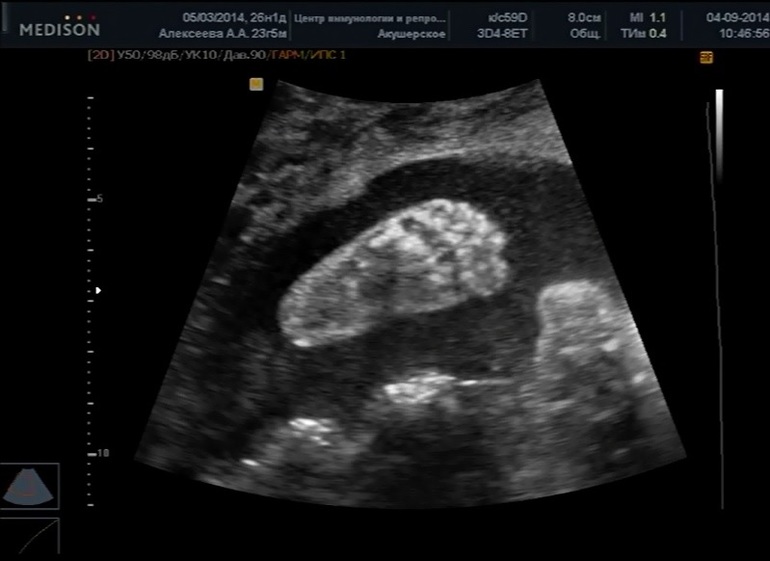

Смутили меня только сроки. Она сегодня ставит нам 24 недели, 730 грамм. А две недели назад в больнице нам ставили 23 недели и 520 грамм. У нас постоянно было на 2 недели меньше, чем по месячным, а сегодня получается, что на три. Отстаем теперь?! Она правда сказала, что по кровотокам все в порядке и что малышке комфортно.

Папина дочка, копия в миниатюре)))

Пяточка, аж 4,7мм! Не много ли?!

Держит свою ножку)))

Наш профиль: